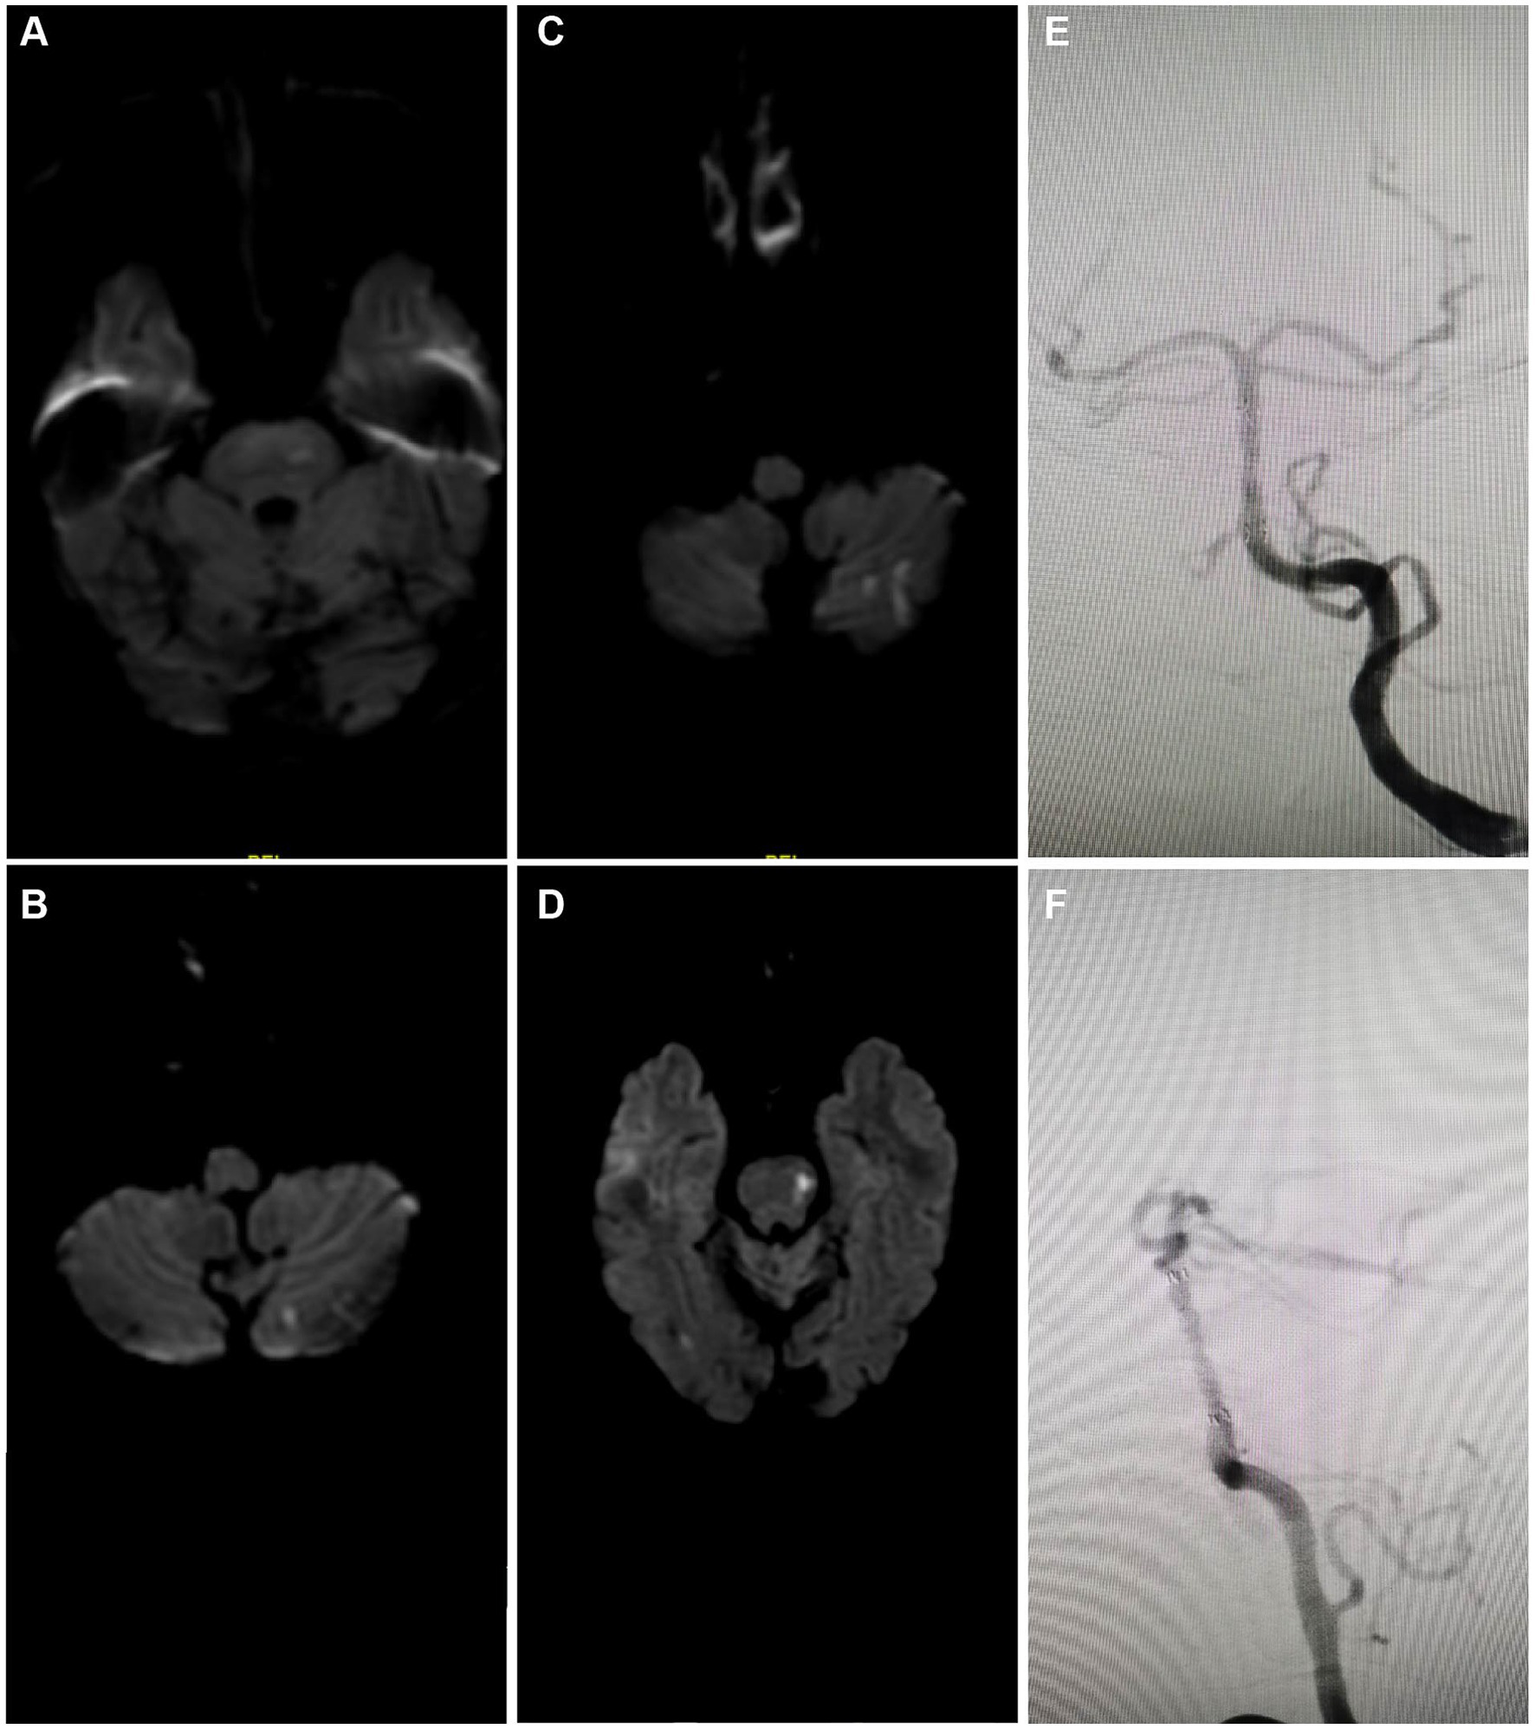

The analysis through serial MRI and DSA depicted the progression of cerebral infarctions at different time points post-treatment with rivaroxaban. Diffusion-weighted imaging (DWI) sequences identified new infarcts in the left pons region at 7 months (Figure 5A) and in the left cerebellar hemisphere at 8 months post-treatment (Figure 5B). Further infarcts were observed at 17 months (Figure 5C) and 24 months (Figure 5D) in the same regions. DSA review at 24 months post-treatment (Figures 5E,F) indicated that the ISR rate at the distal end of the basilar artery where the stent was implanted remained at the preoperative level of approximately 20%, suggesting stable blood flow and no significant restenosis at the stent site. Moreover, 4 out of the 5 patients in the study did not experience recurrent ISR during the follow-up period (Table 2). These imaging findings demonstrate that despite the patency of the local vascular stent, new infarcts still occurred at different post-treatment intervals, suggesting that the recurrence of cerebral infarction under conditions of vascular recanalization may be related to other risk factors, such as hemodynamic changes, vascular pathophysiology, or systemic factors. Therefore, comprehensive dynamic monitoring and management of the patient’s overall condition are required in clinical treatment.

Figure 5

Imaging case analysis of cerebral infarction progression after rivaroxaban treatment. (A) New infarct foci in the left pons region 7 months post-treatment. (B) New infarct foci in the left cerebellar hemisphere 8 months post-treatment. (C) New infarct foci in the left cerebellar hemisphere 17 months post-treatment. (D) New infarct foci in the left pons region 24 months post-treatment. (E,F) 24-month post-treatment angiographic review following rivaroxaban treatment showed the ISR rate at the lower end of the basilar artery where the stent was implanted was approximately the same as preoperative, about 20%.